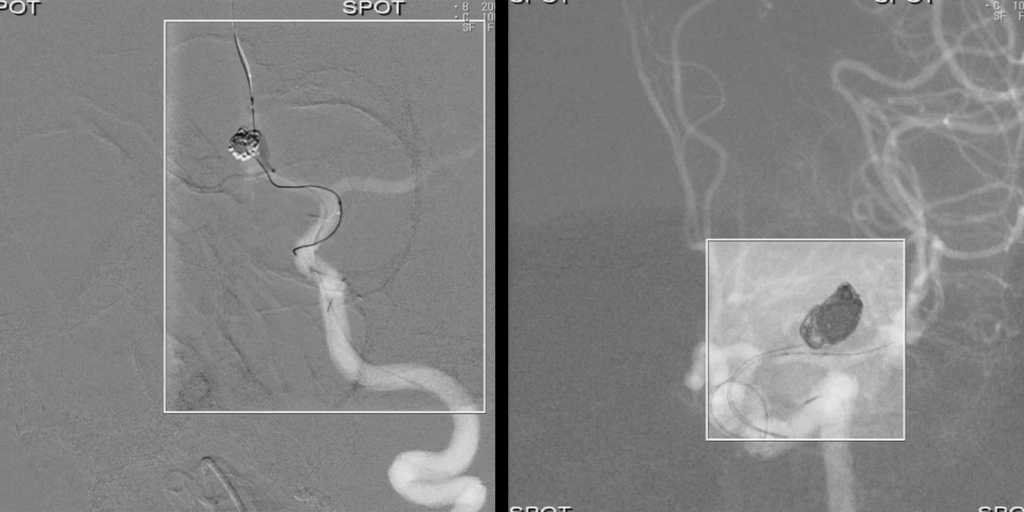

• Режим SPOT ROI допомагає зменшити дозу поза межами області інтересу, одночасно дозволяючи візуалізувати навколишню анатомію завдяки застосуванню спеціального фільтру. Відображення не лише пристрою, а й навколишньої анатомії під час встановленняпристрою є дуже важливим для успішного результату.

4. Численні програми для кількісного аналізу зображень, програми для покращення візуалізації стентів, програми для аналізу дозового навантаження, функції отримання, аналізу та накладання 3D-зображень, програми для оцінки перфузії судин та широкі можливості постробробки – прокриють усі, навіть найвибагливіші потреби.